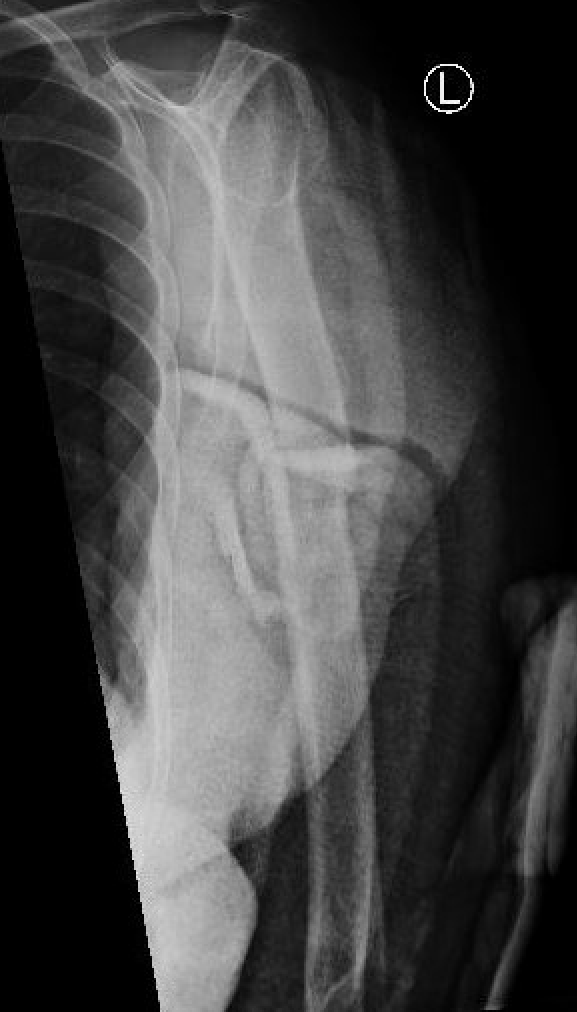

Management Nonunion Humerus Fractures

Background

Definition

Mean time to union is 13 weeks

No evidence of callous on xrays taken 6 - 8 weeks apart

Fracture patterns

- highest risk is transverse fractures

- proximal humerus shaft fractures also at risk due to displacing force of pectoralis and deltoid, and LHB may interpose